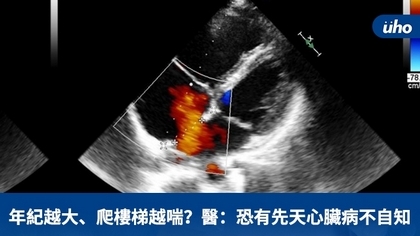

(優活健康網新聞部/綜合報導)一名20幾歲年輕女性,近來爬樓梯感覺會喘,經過健康檢查發現有心雜音狀況;另一位60歲女士也有同樣情況,平時活動偶爾會喘,健檢之後發現心臟擴大。這2個案例至心臟科門診檢查後,經醫師診斷是「心房中膈缺損」需手術。 心臟血液跑到肺動脈致右心室衰竭新竹台大分院小兒部小兒心臟科醫師傅俊閔說明,「心房中膈缺損」是一種先天性心臟病,正常人左心房與右心房互不連通,由心房中膈隔開,若是心房中膈有破洞就稱為「心房中膈缺損」。傅俊閔解釋,心房中膈缺損會造成血液經此破洞從左心房流到右心房、右心室再到肺動脈,導致右心室與肺動脈擴大,因而會產生活動耐受性降低、容易喘等右心室衰竭症狀,嚴重甚至可能導致肺動脈高血壓等嚴重併發症,需要積極治療。 年輕時沒有明顯不適  健檢時才發現問題多數患者在年輕時可能沒有明顯不適,或者健檢時僅發現輕微心雜音,隨著年齡增長才出現較明顯症狀。因此有些人到成年,甚至中老年後才被診斷出有心房中膈缺損。傅俊閔表示,心房中膈缺損根據缺損所在之解剖位置分類,其中第二型心房中膈缺損,可利用心導管手術將其關閉,效果好且恢復快,只有腹股溝會有個小傷口。其他型的心房中膈缺損則因為破洞位置較不適合關閉器放置,仍有可能需要傳統手術治療。 新竹台大分院小兒心臟科團隊過去幾年與該院麻醉科合作,已陸續成功完成多例「經心導管心房中膈缺損關閉手術」和「開放性動脈導管關閉手術」,前述2名病人也在傅俊閔安排心導管手術後,順利關閉心房中膈缺損,術後皆恢復良好,目前持續於門診追蹤。

(優活健康網記者張桂榕/綜合報導)心房中膈缺損是常見的先天性心臟病,但卻不易被診斷出來。大約1000個出生的新生兒,有一個到兩個會出現心房中膈的破洞,就是心房中膈缺損。大部分的心房中膈缺損在兩歲之內,都有機會自行關閉。但有些心房中膈缺損破洞較大,無法自行關閉,並會隨著年紀長大,破洞越來越大,造成致命的危險。所以這疾病就像是一顆隱藏的地雷,有可能在兒童也有可能在成人發病,不可不慎!心導管手術置放關閉器 隔絕血液分流台東馬偕小兒心臟科游昌憲醫師在美國費城兒童醫院學習更精進的小兒手術技術,受訓後引進心導管關閉術,解決這些病人的心中大患!游醫師表示,心導管關閉術的操作,關閉器就如同一支雨傘一般,當導線伸進心房中膈破洞位置,即將原本藏在導線頂端的關閉器展開並將破洞修補。心導管手術只在鼠蹊部的地方有一微小的血管穿刺傷口,手術後無須縫合,因此恢復很快,縮短住院時間,肚子不會留下疤痕。心房中膈缺損為先天性心臟病的一種心房中膈缺損是指左心房與右心房間的中膈有破洞,導致左心房到右心房血液分流。長期過度分流可能導致右心房與右心室擴大,病人可能因此有右心室衰竭症狀,如喘、呼吸不順、運動不適等,更嚴重可能併發肺動脈高血壓。阿美族陸小弟弟,於出生4個月時發現哭鬧時臉上會發紫,經診斷患有「複雜性的先天性心臟病」,但今年發現心房中隔缺損破洞變大,由游昌憲醫師在台東馬偕以「心導管關閉術」予以處理。術後的陸小弟弟恢復非常好,每天活動力都很旺盛。先天性心臟病患 應早期治療另一位46歲卑南族青年,一次在打籃球當中,突然胸悶不適,被友人送醫急救。經由游昌憲醫師使用心導管關閉術成功處理。游醫師表示:先天性心臟病在兒童期症狀不明顯,然而隨著年紀到達30至40歲,逐漸出現心悸、呼吸急促,及運動容易疲倦的表現;不幸的是,這些症狀代表肺動脈已出現不可逆的病變,造成肺動脈高壓,心房中膈缺損的血流流向也從左至右分流,逐漸變成右至左分流。這時候要再關閉這個破洞,反而會造成心臟衰竭,增加病人猝死的風險,最後必需做心肺移植的手術才能拯救生命。故心房中膈缺損雖是較容易處理的心臟病,但若未早期發現及早期治療,仍會對我們的健康造成重大的影響。致力於提昇小兒科重症醫療的游昌憲醫師,幾乎每年都至全台東縣國小一年級、四年級,以及國中一年級,作三階段的心臟篩檢,其目標就是要早期發現此心房中膈缺損,以期早期治療這類病人。盼望藉著每年的學童心臟病篩檢,能夠早期診斷此類心臟病。

(優活健康網新聞部/綜合報導)李先生日前因為胸口不適至心臟科就診,經心臟超音波檢查後發現為心房中膈缺損。經心房中膈缺損關閉心導管手術,李先生手術後恢復良好,相關不適症狀也有明顯改善。心房中膈兒童期可能無症狀或不明顯 成人期才確診台大醫院新竹分院小兒部兒童心臟科醫師傅俊閔表示,心房中膈缺損為先天性心臟病的一種,是指左心房與右心房間的中膈有破洞,導致左心房到右心房血液分流。長期過度分流可能導致右心房與右心室擴大,病人可能因此有右心室衰竭症狀,如喘、呼吸不順、運動不適等,更嚴重可能併發肺動脈高血壓。大部分心房中膈缺損導致的血液分流並不顯著,在兒童時期,臨床可能沒有症狀或症狀不明顯,可能只有輕微心雜音或心電圖異常。因此有不少人可能如上述李先生一樣,到成人階段因為出現症狀,才發現患有心房中膈缺損。心導管手術置放關閉器 隔絕血液分流傅俊閔醫師說明,診斷為心房中膈缺損後,如果血液分流量較大,或併發肺動脈高血壓,就要考慮積極治療。目前標準的建議治療是以心導管手術置放關閉器,阻絕2個心房間的血液分流。手術當可能需要麻醉醫師助,在全身麻醉下使用經食道超音波,確認心房中膈缺損的大小與位置,挑選適當大小的關閉器,並在置放後確認關閉器位置適當且成功隔絕心房間的血液分流。心導管手術只在鼠蹊部的地方有一微小的血管穿刺傷口,手術後無須縫合,因此恢復很快,一般住院3到4天即可。相較於傳統開心手術,經心導管「心房中膈缺損關閉術」,其具有免開刀的優點,且安全性及成功率高。